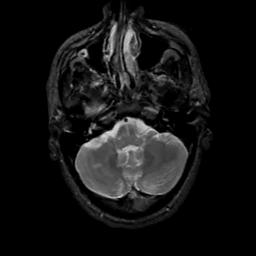

MR Study #12, May 12, 1991 -- Slice #10

[Home][Help][Clinical][Tour 1][Tour 2] Slice 10